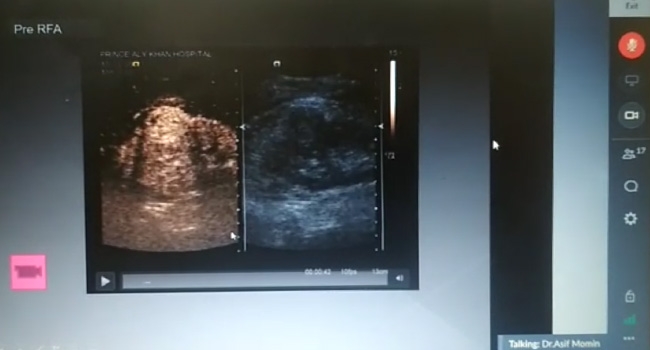

Trivitron & Kiran conducted a Clinical Webinar session on 18th December on the topic - “Contrast Ultrasound in Interventional Radiology”, presented by Dr. Asif Momin – HOD Radiodiagnosis, Prince Aly Khan Hospital – Mumbai. The Webinar was attended by Radiologists and Customers of Trivitron & Kiran and the initiative was well appreciated by all the attendees. Trivitron & Kiran conducted a Clinical Webinar session on 18th December on the topic - “Contrast Ultrasound in Interventional Radiology”, presented by Dr. Asif Momin – HOD Radiodiagnosis, Prince Aly Khan Hospital – Mumbai. The Webinar was attended by Radiologists and Customers of Trivitron & Kiran and the initiative was well appreciated by all the attendees.